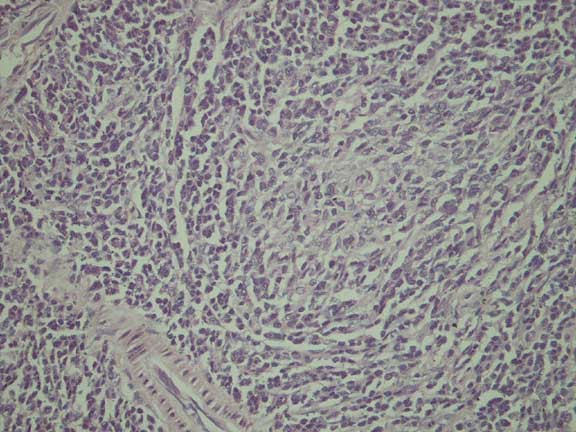

Spleen - Frozen

Haematoxylin & Eosin (x400)